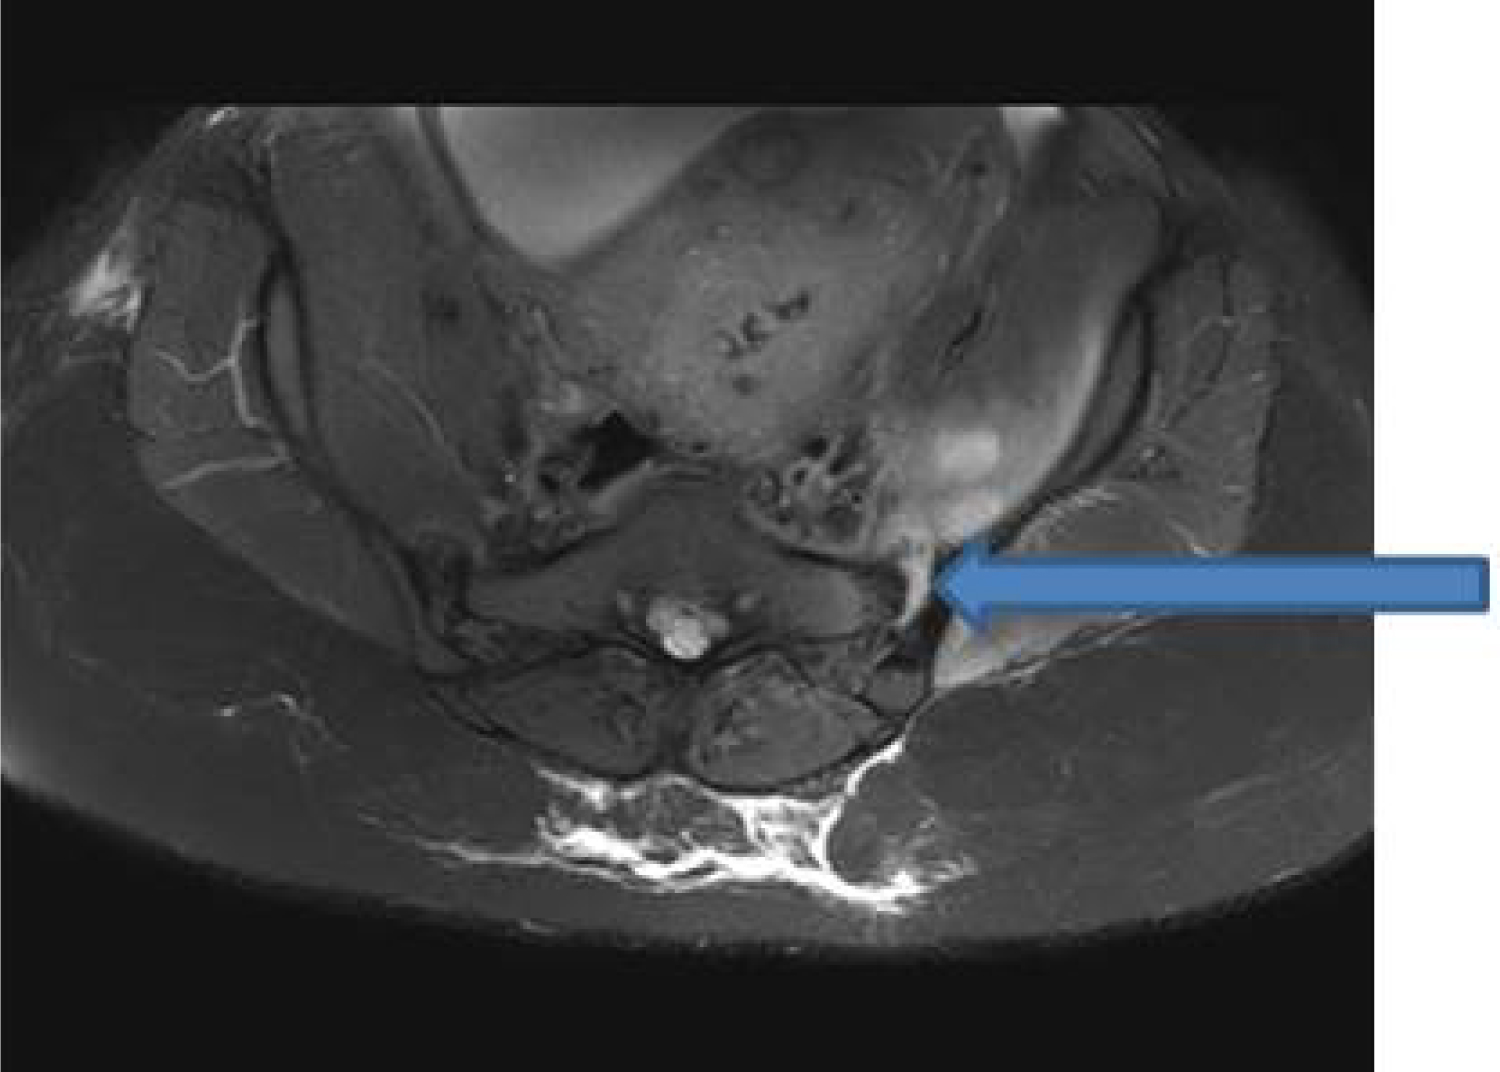

In light of recent epidural catheter placement, an urgent magnetic resonance imaging (MRI) of the lumbar spine with contrast enhancement was ordered. No evidence of epidural hematoma or abscess was present. However, incidental findings of asymmetric fluid distention of the left sacroiliac (SI) joint (Figure 1) with fluid collections within the left iliopsoas, left piriformis, and left gluteus muscles (Figure 2) were detected, findings concerning for infectious/inflammatory sacroiliitis (ISI). Neuroradiology consult was placed, and under computerized tomography (CT) guidance, about 10 ml of purulent fluid was aspirated from left SI joint, and sent for Gram stain and culture. Infectious Disease consult was placed and the patient was started on empiric vancomycin pending culture results. Further work up included measurement of erythrocyte sedimentation rate (ESR), and C-reactive protein (CRP), both were found to be about three fold elevated. Blood cultures were drawn but reported later as negative for any growth. Gram stain of SI joint fluid revealed Gram positive cocci that on culture were identified as group B streptococci (Strep. agalactiae). Vancomycin was changed to ceftriaxone per sensitivity results. An orthopedic consult for septic arthritis was also placed, but conservative management was recommended in light of clinical (decreasing pain), and laboratory (resolving leukocytosis, decreasing ESR and CRP) improvement. The patient was discharged home on long term (6 weeks) intravenous antibiotics and recommended to follow up as instructed.

Figure 1: Fat saturated T1-weighted axial image showing asymmetric fluid distention of left sacroiliac joint (blue arrow). View Figure 1